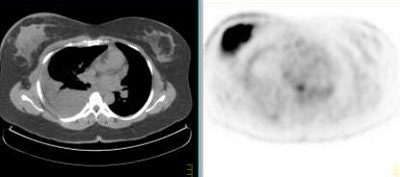

Above, multiple axillary nodal metastases, SUV all > 2.3. Below, primary breast tumor with SUV 7.4. Images courtesy Dr. Alan Waxman.

![]() |